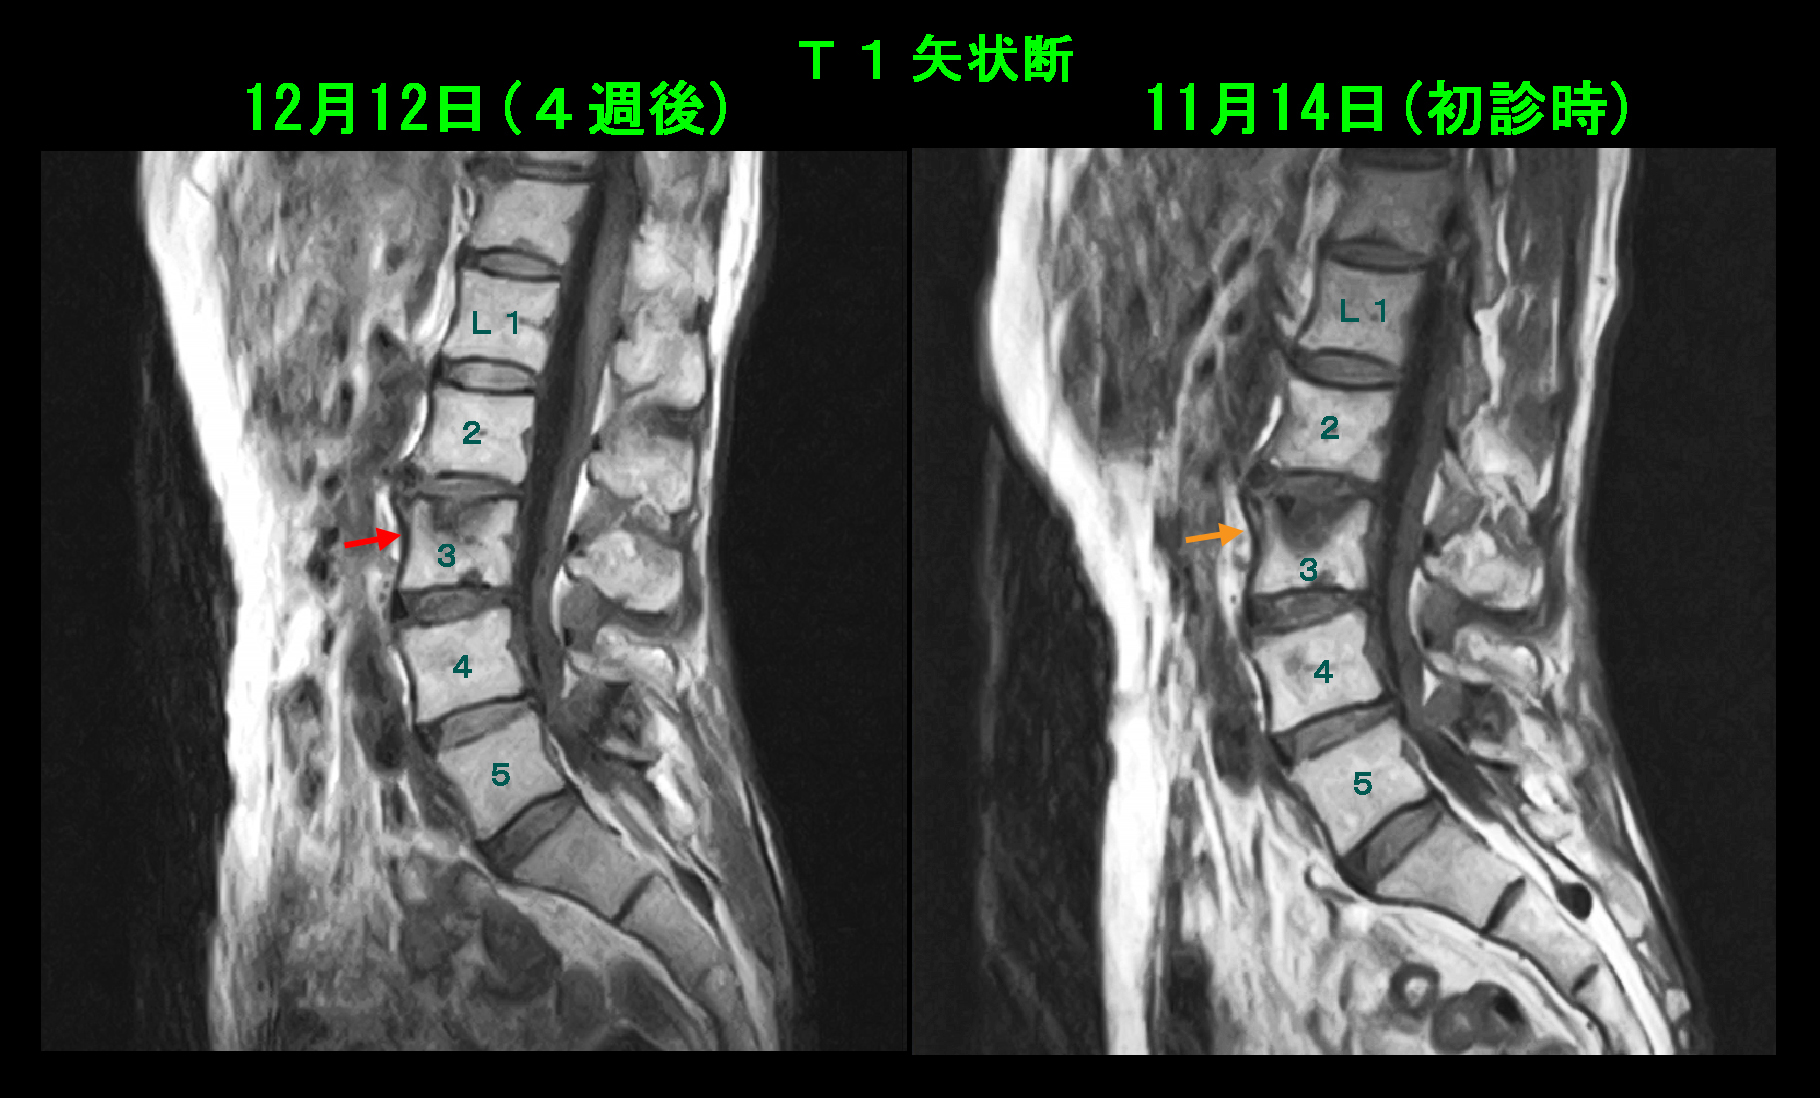

73才女 MR1.jpg

MRI検査では予想通りにL45レベルで脊椎は圧迫されており(オレンジ矢印)、腰部脊柱管狭窄症と診断される状態でした。しかし、L3椎体の上縁がT2矢状断ではV字に白く陥凹しており(高輝度化の所見)、T1矢状断では黒くなっており(低輝度化の所見)、椎体の骨の輪郭が明瞭ではありません。これは54才の男性の腰骨の損傷と同じ状態がもう少し悪化した状態と理解されます。54才男性は椎体損傷が発症して翌日に受診されていますが、この女性は半年間の期間がありますから、損傷状態がよりひどくなっていても仕方ないと思われます。私はこの患者さんの腰痛は脊柱管狭窄による腰痛ではなく、L3椎体の損傷に起因する腰痛であると診断しました。54才の男性に処方した薬剤を処方するとともに、8週間運動を休止しましょうと指示しました。

73才女 MR2.jpg

8週後のMRI再検査の画像を提示します。T2矢状断ではL3椎体の高輝度所見は軽減化しており、上縁の皮質骨の黒い線が認識可能となっています。これは壊れたL3の上縁の皮質骨が修復されたことを意味しています。